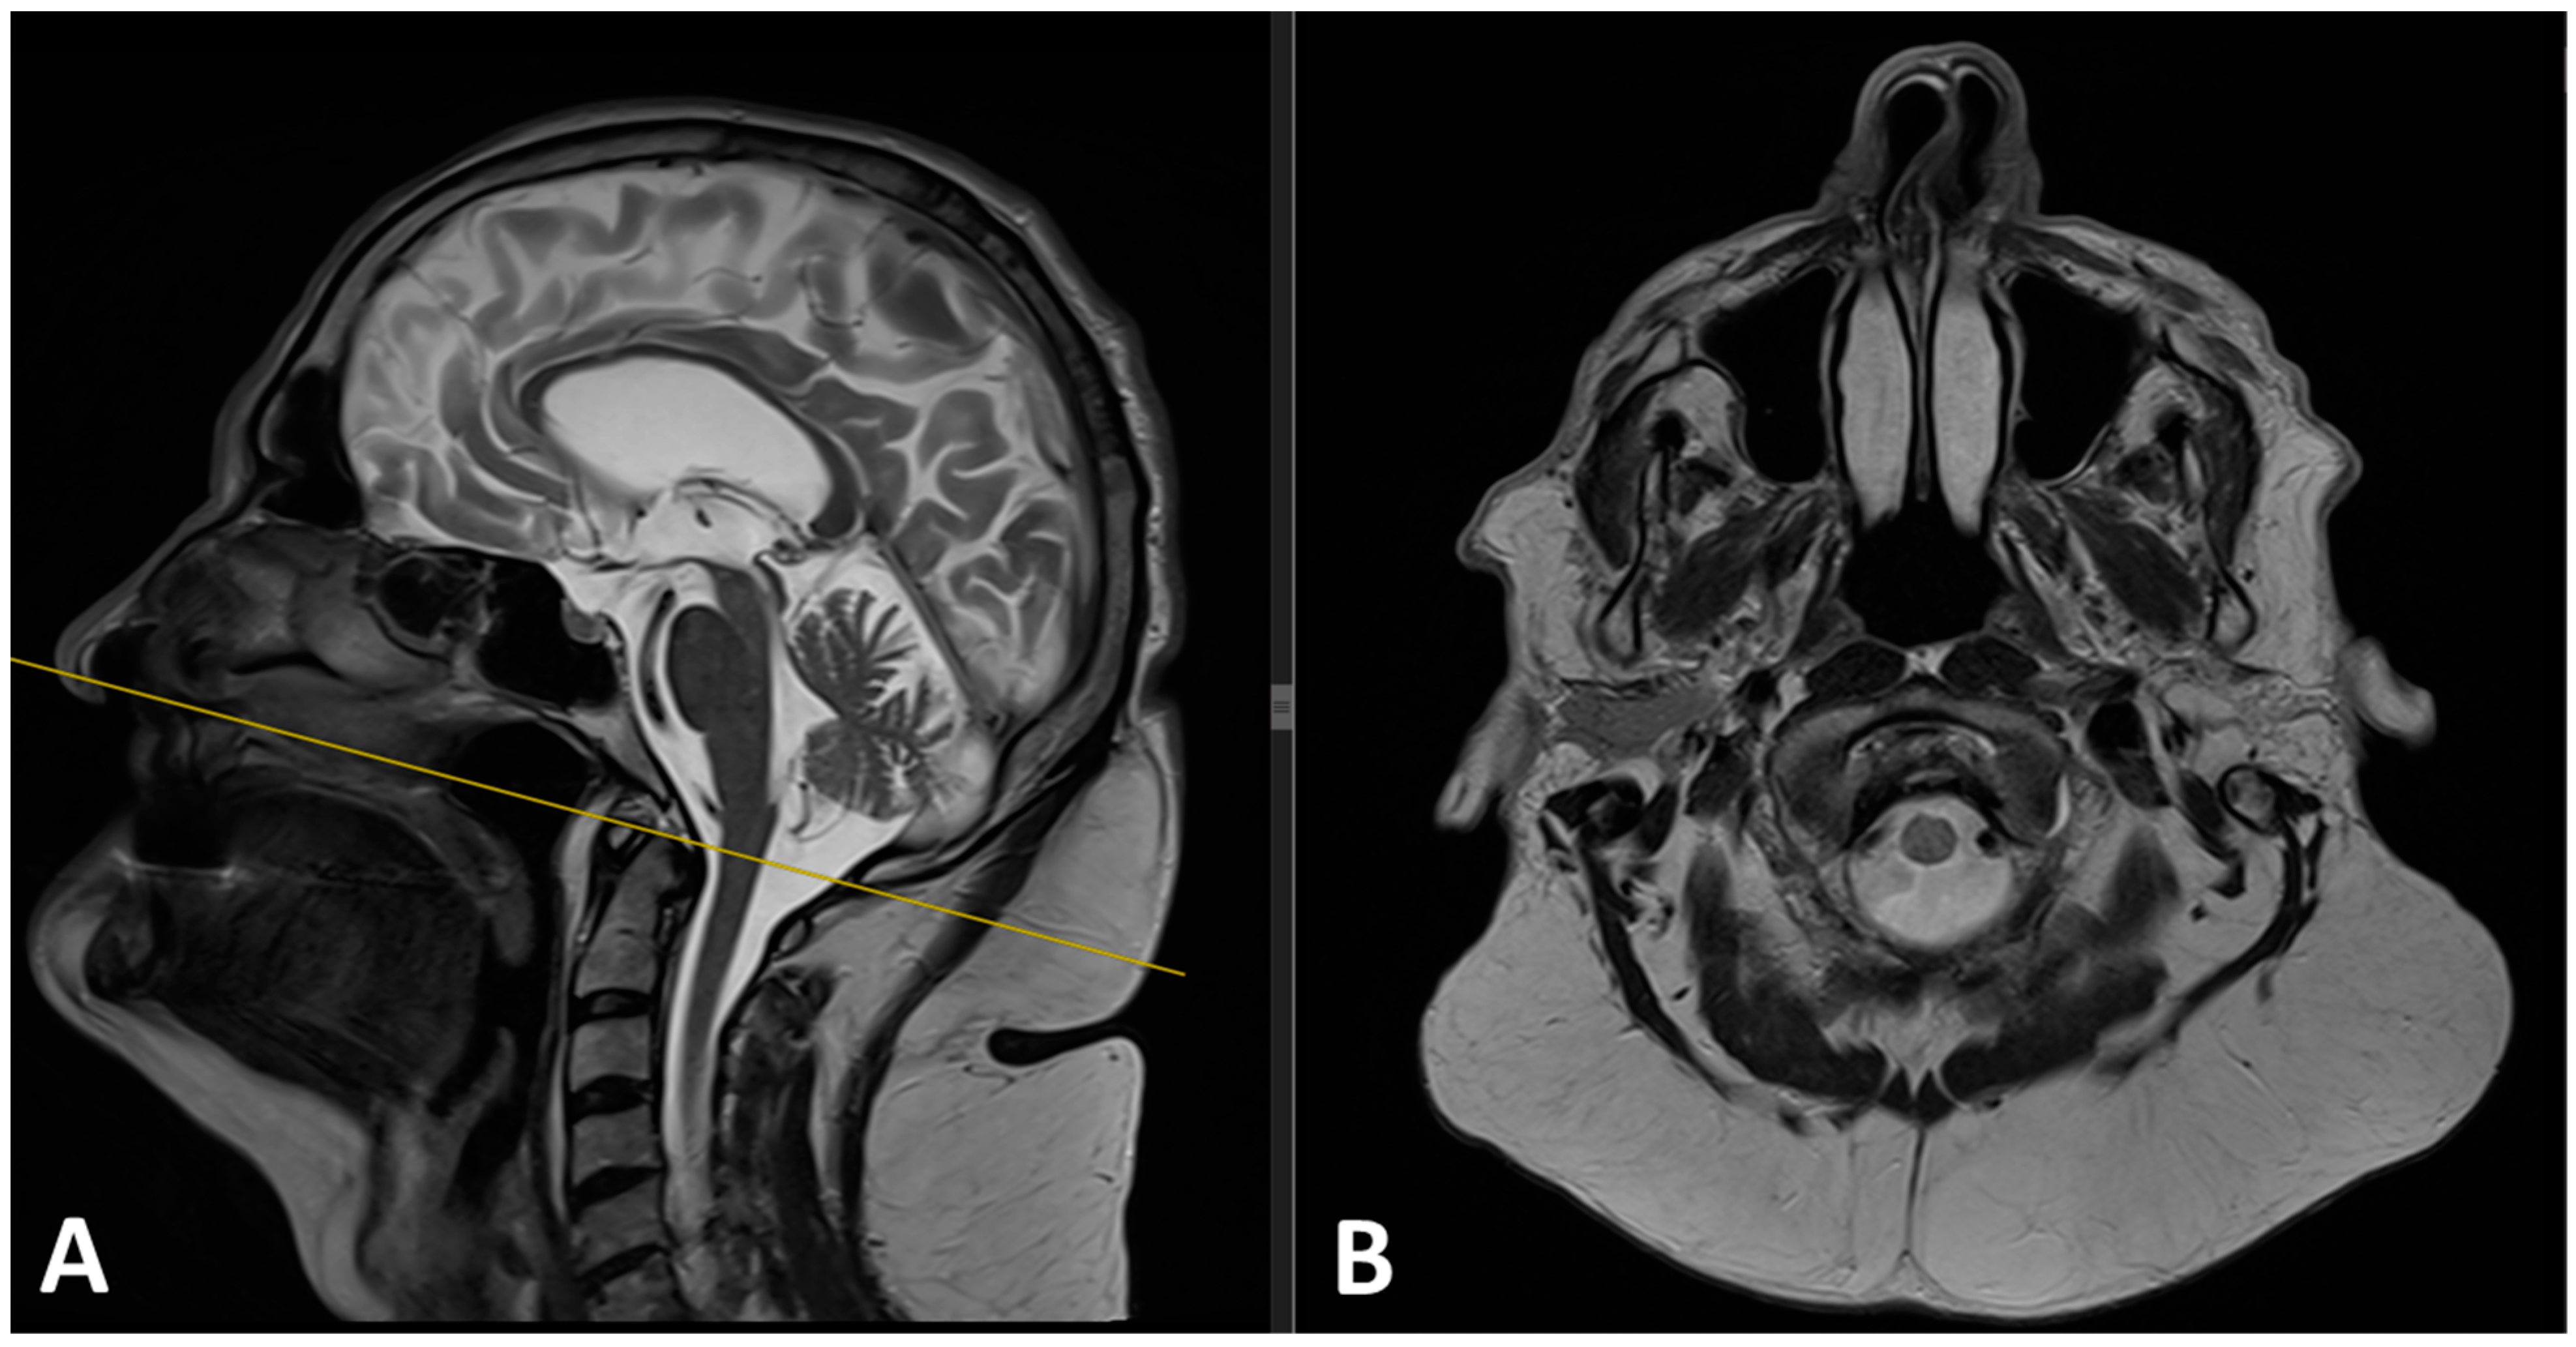

2.2. Imaging Studies

3.4. Diagnosis